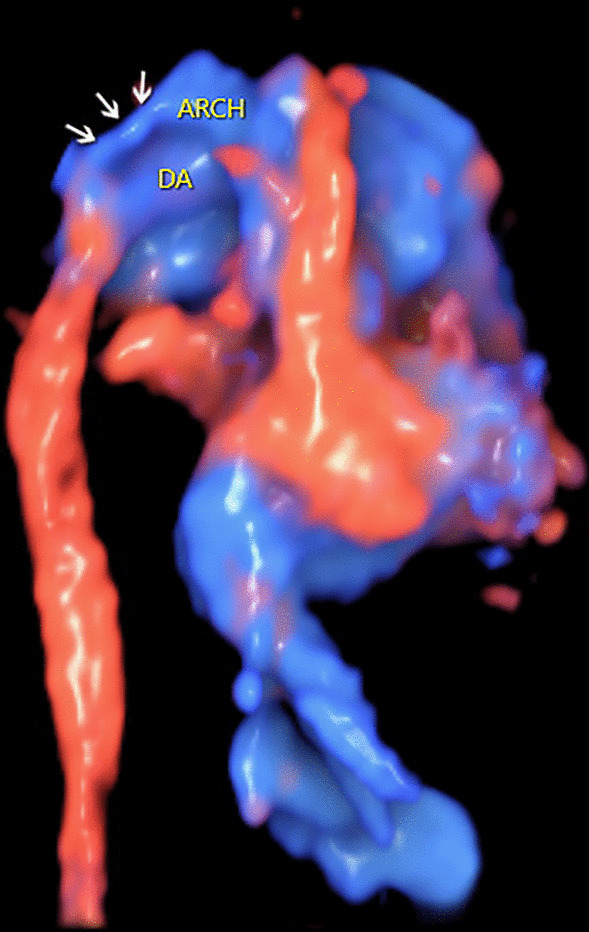

Fig. 4.

The 3D reconstructed image showing the great arteries of the fetus with coarctation of the aorta. The 3D rendered image clearly shows the great arteries in space. In addition, it demonstrates a sharp angle between the aortic arch and the slim isthmus (indicated by the arrows). Arch: aortic arch; DA: ductus arteriosus

A 32-year-old woman, gravida 3, para 1, was referred to our center at 26 + 3 weeks of gestation for further fetal cardiac examination for suspected cardiac anomalies. The patient was in good health without any maternal complications or high-risk factors (e.g. diabetes, hypertension, amniotic disorders). A detailed echocardiogram was performed to find any potential cardiac anomalies using transverse and sagittal scanning. Conventional 2DE was used to show fetal anatomical structures. Color Doppler flow imaging (CDFI), together with HDFI was used to show fetal hemodynamics. The sound beam was continuously moved upward along the vertical axis of the fetal thorax to perform the transverse scanning. The four-chamber view (4CV) showed a symmetrical left and right heart. The left and right outflow tract views showed normal ventriculoarterial connections. However, a small-sized ventricular septal defect (VSD) was identified at the 4CV and the left outflow tract view with the communication clearly shown by CDFI (Fig. 1). An additional movie file shows this in more detail (See Additional file 1: Video). The pulmonary valve annulus (PVA) was apparently wider in comparison with the aortic valve annulus (AVA). The ratio of PVA/AVA was 1.6 in diameter. The size of the pulmonary artery (PA) was also larger than the aorta (AO) and the ratio of PA/AO was 2.1 in diameter. At the three-vessel trachea (3VT) view, the widened pulmonary trunk continued to be the ductus, which was connected with the descending aorta. At the same time, a tiny vessel was found located at the right side of the pulmonary trunk, with no convergence with the ductus (Fig. 2). An additional movie file shows this in more detail (See Additional file 2: Video). Under normal conditions, the aortic arch joins with the ductus to form proximal descending aorta in a characteristic “V” shape at the 3VT view [2]. The echocardiographic manifestations in the current case thus suggest the possibility of an IAA. Sagittal planes were also scanned to obtain more information. The arch did not present, instead, the ascending aorta was visualized going straight upward and then branching three brachiocephalic arteries in a “W” shape (Fig. 3). An additional movie file shows this in more detail (See Additional file 3: Video). A preliminary diagnosis of IAA type A was then reached. The 3DE with STIC technology was then used to obtain 3D images of the great arteries to confirm the 2D diagnosis. A 3D motorized transducer (4–8 MHz) was used to acquire cardiac volumes when scanning the sagittal planes using HDFI. The acquisition time was set to 12.5 s and the sweep angle was set to 30°. Cardiac volumes were acquired automatically and then reconstructed to display in a cine loop in multiplanar mode. Volume post-analysis was then performed using an off-line software (4D viewer, version 14.0) to obtain the 3D reconstructed images. This could be achieved by properly adjusting the direction and size of the region of interest (ROI) and the rotation of the images in three orthogonal planes in the volume. A combination of smooth surface and gradient light algorithms was also used to enhance the 3D effect of the reconstructed images. The 3D image demonstrated an abnormal angle of attachment of the aortic arch to the ductus and descending aorta via a slim isthmus (Fig. 4). An additional movie file shows this in more detail (See Additional file 4: Video). The final diagnosis was CoA at the isthmus.

Additional file 4. Video. The 3D rendered image cine loops showing the great arteries in a fetus with coarctation of the aorta. The 3D rendered image clearly shows the great arteries in space. In addition, it demonstrates a sharp angle between the aortic arch and the slim isthmus (indicated by the arrows). Arch: aortic arch; DA: ductus arteriosus.